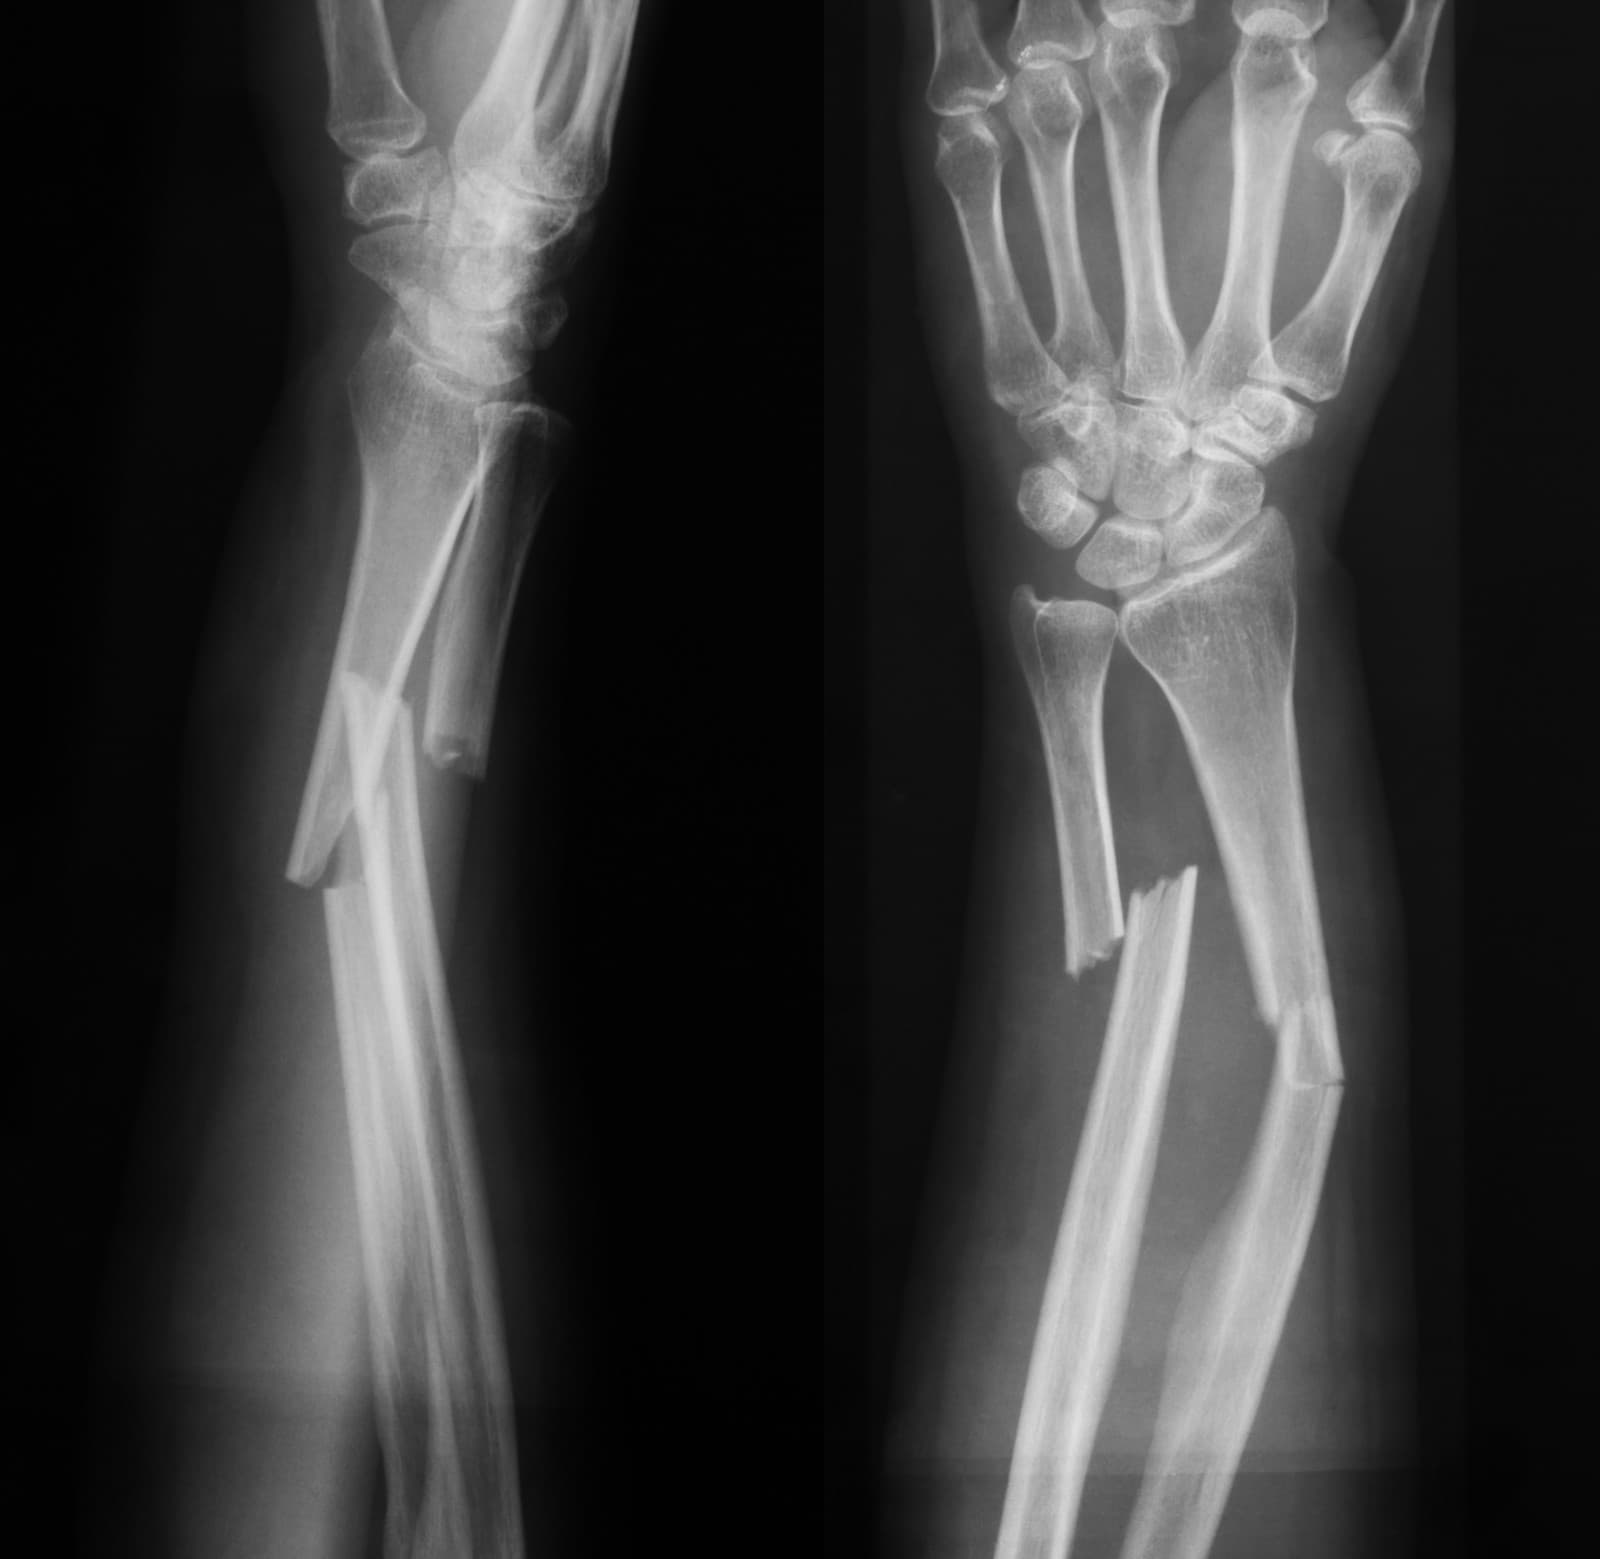

Ilustračný obrázok Zobraziť galériu (2)

(Zdroj: Getty Images)